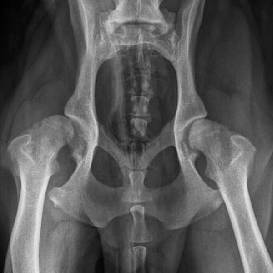

Kyčelní kloub psa plemene labrador před operací a po operaci totální endoprotézy Aesculap na RTG snímcích

B. Braun Medical v tomto roce na výstavě představil kromě klasického portfolia produktů divize Hospital Care i letošní novinku na veterinárním trhu - kompletní systém totální endoprotézy pro psa, značky Aesculap. Tato endoprotéza zaujala při své premiéře přední veterinární odborníky, a výsledkem je první workshop, který se uskuteční ve dnech 20.-21. června na veterinární klinice MVDr. Rašky v Ostravě pod odborným vedením zkušených operatérů tohoto systému z Norimberské veterinární kliniky. Ta je po Mnichovské univerzitě největším veterinárním pracovištěm Bavorska.